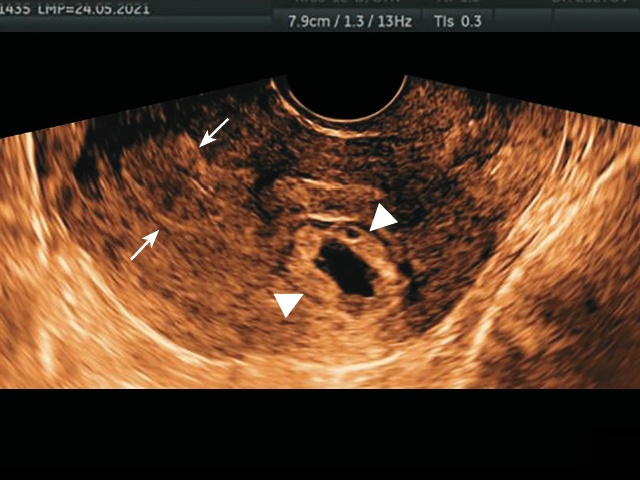

Картина шейки матки в норме. На поперечном срезе матки справа в проекции трубного угла, отдельно от границы эндометрия обнаружено округлое образование размерами 25х20 мм, подобное ПЯ: центральное жидкостное включение диаметром 8 мм с утолщенным контуром повышенной плотности и повышенной васкуляризацией (рис. 5). На этой же эхограмме обращает на себя внимание деформация контура серозной оболочки матки выбухающим краем ПЯ.

а) отражена картина ПЯ в виде эхогенной округлой массы с центральным жидкостным включением (наконечники стрелок), расположенной отдельно от полости матки (стрелки) и деформирующей с латеральной стороны наружный контур матки.

б) отражен перитрофобластический кровоток вокруг ПЯ.